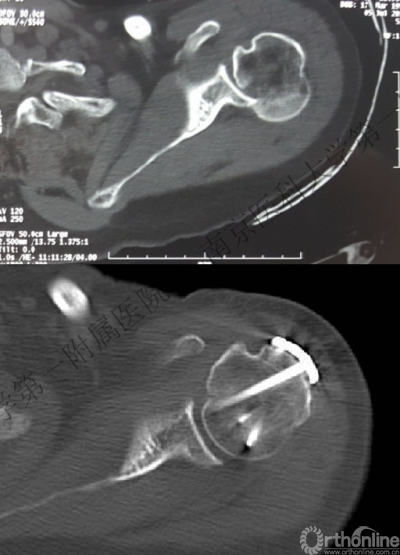

2.肩关节CT

确定肩关节后脱位。

了解反Hill-sachs损伤和程度。

观察肱骨近端主要骨折线和次要骨折线及形态。

(三)肱骨小结节截骨

显露更为充分,小结节骨块可用于修复反Hill-Sachs损伤;但增加了骨折复位的难度。伴有小结节骨折时更便于处理。

(四)复位脱位的肱骨头

1.用两枚3.5mm克氏针钻入肱骨头内,固定主要的肱骨头骨折块并把持肱骨头,利用Joy-Stick技术将肱骨头牵开、外旋、复位。

(五)修复反Hill-Sachs损伤

1.外旋肱骨头,显露肱骨头关节面损伤处。

2.改良McLaughlin术、 Underpinning术、球囊扩张术。

3.Dubousset 方法:对肱骨头关节面压缩性骨折均给予直视下复位、填充植骨、螺钉固定,手术指征不受压缩部分占总关节面面积比例的限制。